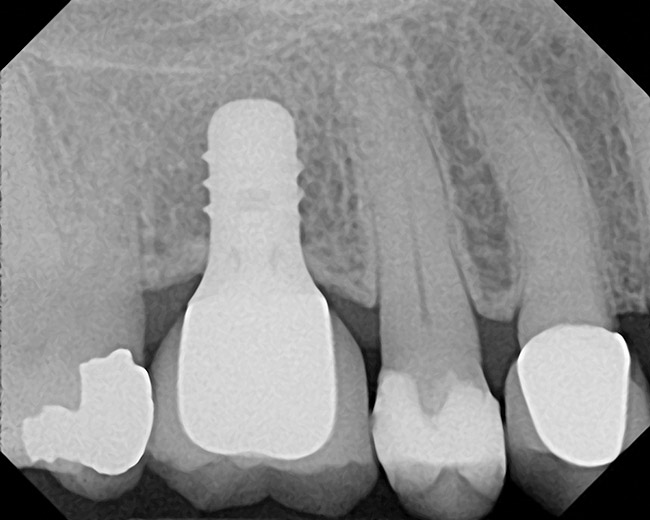

The patient was a 71-year-old man with significant caries and subsequent bone loss associated with tooth No. 30. The septal bone was lost, with the exception of the coronal aspect, resulting in a "bridge of bone" connecting the buccal and lingual cortices of the site (Figure 1). After reflection of the full-thickness buccal and lingual flaps, extraction, and manual and ultrasonic debridement of the socket to remove all visible soft-tissue remnants, the defect was obturated with the rhBMP-2/ACS material (Figure 2).